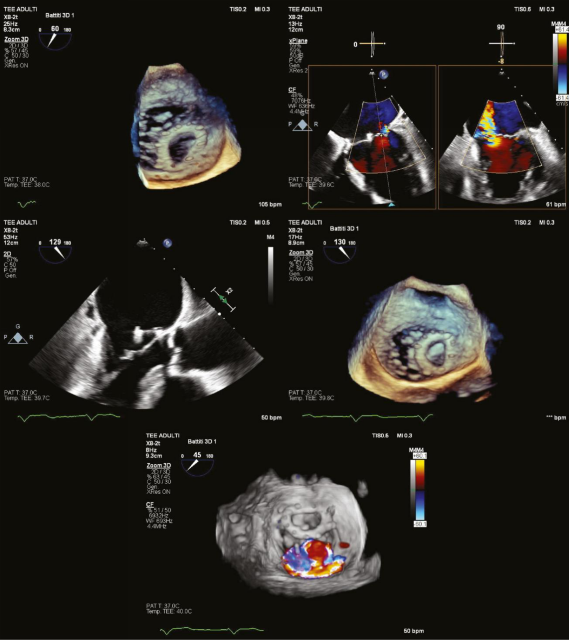

图片

手术历时90分钟,经右股静脉入路,在经食道超声(TEE)和透视引导下完成房间隔穿刺。PASCAL Ace装置成功锚定于二尖瓣A2-P2段,避开脱位成形环,未发生器械卡压或并发症。术后超声证实残余反流为轻度(1+/4),平均跨瓣压差3.6 mmHg,二尖瓣有效面积3.5 cm²。患者术后6天出院,仅1天ICU监护。

病例讨论与启示成形环脱位是二尖瓣修复术后罕见但严重的并发症,常因缝线断裂、感染或长期血流冲击导致。传统处理需开胸手术(更换成形环或行瓣膜置换),但二次手术死亡率高达10%-15%。本病例通过经皮介入成功规避了开胸风险,凸显TMVR在高危人群中的替代价值。与MitraClip相比,PASCAL系统的“Spacer”设计可填充瓣叶间隙,独立抓取臂(“Clasp”)允许分步夹合,更适合解剖复杂的病例(如脱位环遮挡或钙化瓣叶)。本病例中,术者利用TEE实时三维成像精准导航,将装置置于脱位环下方,避免了器械干扰,体现了影像引导的关键作用。